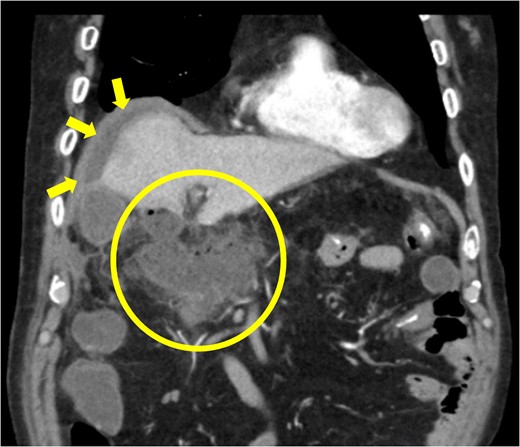

The amylase levels of drainage fluid and blood at postoperative day (POD) 1 (Ascites 6980 IU/dl, Serum 1123 IU/dl) and POD 3 (Ascites 673 IU/dl, Serum 487 IU/dl) revealed pancreatic fistula based on the criteria of International Study Group of Pancreatic Fistula [2]. After that, their results improved, and fluoroscopy showed no stenosis and leakage. Therefore, we removed all drains at POD 8, however the following day, the patient developed high fever. Plain CT revealed intraperitoneal fluid around subdiaphragmatic and duodenal stump (Fig. 3). We inserted a pig-tail drainage tube to the subdiaphragmatic space (Fig. 4). Since biliary fluid was discharged through the tube, we suspected duodenal leakage and started infusion of somatostatin analogs and antibiotics. At POD 13, the patient complained of whole abdominal pain with peritoneal signs. As the patient became hemodynamically unstable, we performed emergent laparotomy to lavage and insert multiple drainage tubes. Two perforation pinholes were identified in the anterior wall of the duodenum, near the stump. We resected the vulnerable duodenal stump including the perforation site and closed by Gambee’s method with unabsorbable 4–0 proline (Fig. 5). We inserted multiple drainage tubes (Fig. 6a): a C-tube from the cystic duct into the common bile duct to separate biliary juice and pancreatic juice, a dual drainage tube around the duodenal stump with continuous suction (Fig. 6b), a simple intraluminal drainage tube via the duodenum near the stump through a new skin incision on the left side of the abdomen for duodenal decompression, and a drainage tube into the rectovesical pouch. After the reoperation, we irrigated the cavity around the duodenal stump through each drain with saline. Since the contrast agent did not flow into the duodenum and the cavity around the duodenal stump gradually got smaller (Fig. 7), oral intake of fluid diet was initiated at POD 37. However, fistulography at POD 44 showed that the fistula of duodenal stump had relapsed (Fig. 8). Although we considered performing second reoperation for duodenal stump closure, due to the cavity around the duodenal stump was located, we continued conservative management and irrigation via drainage tubes. Fistulography demonstrated no leakage from the duodenal stump at POD 56, and the patient discharged at POD 59.

Diagnosis of postoperative duodenal perforation. CT showed ascites in subdiaphragmatic space (arrow) and around duodenal stump (circle) at POD 8.